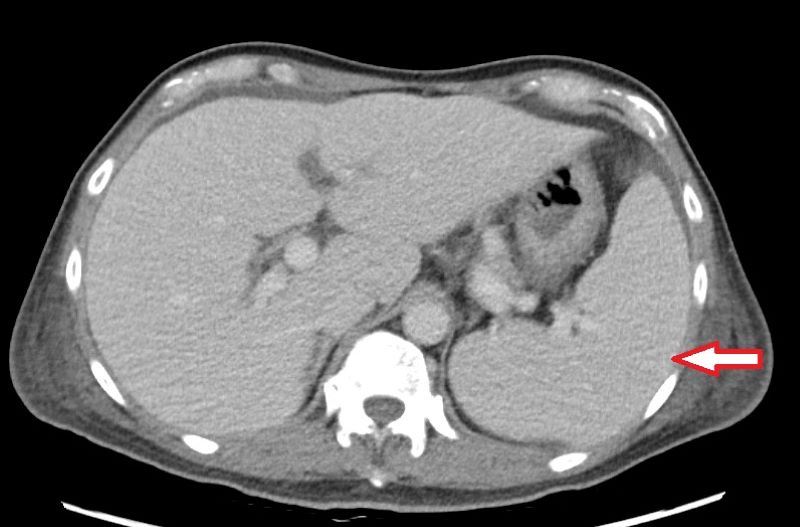

63歲的林先生去年底開始出現不明原因的反覆高燒,多次奔波診所求診始終找不到原因,後至醫院感染科就醫。抽血檢查顯示白血球、血小板及血紅素低下,必須輸血,但血液及骨髓等相關檢查均找不到病因,僅電腦斷層意外發現脾臟腫大與腹水。最後在住院的心臟超音波檢查中發現林先生罹患三尖瓣重度閉鎖不全,瓣膜上還長了一公分大的贅生物(即細菌感染的病灶),確診為感染性心內膜炎。會診心臟血管外科後更換人工生物瓣膜、同步清除感染病灶。病人血球數值明顯回升,順利恢復健康。

他說,若三尖瓣功能受損,血液逆流回右心房,使右心房壓力增加,進而影響全身血液回流,就會導致器官壓力上升,當逆流非常嚴重且延遲治療,少部份病人甚至可能導致肝脾出現問題,如肝硬化、脾臟腫大等。而脾臟是造血器官,若因此腫大造成血球細胞破壞,就可能導致全身性血球減少,發生如林先生一般的情況。